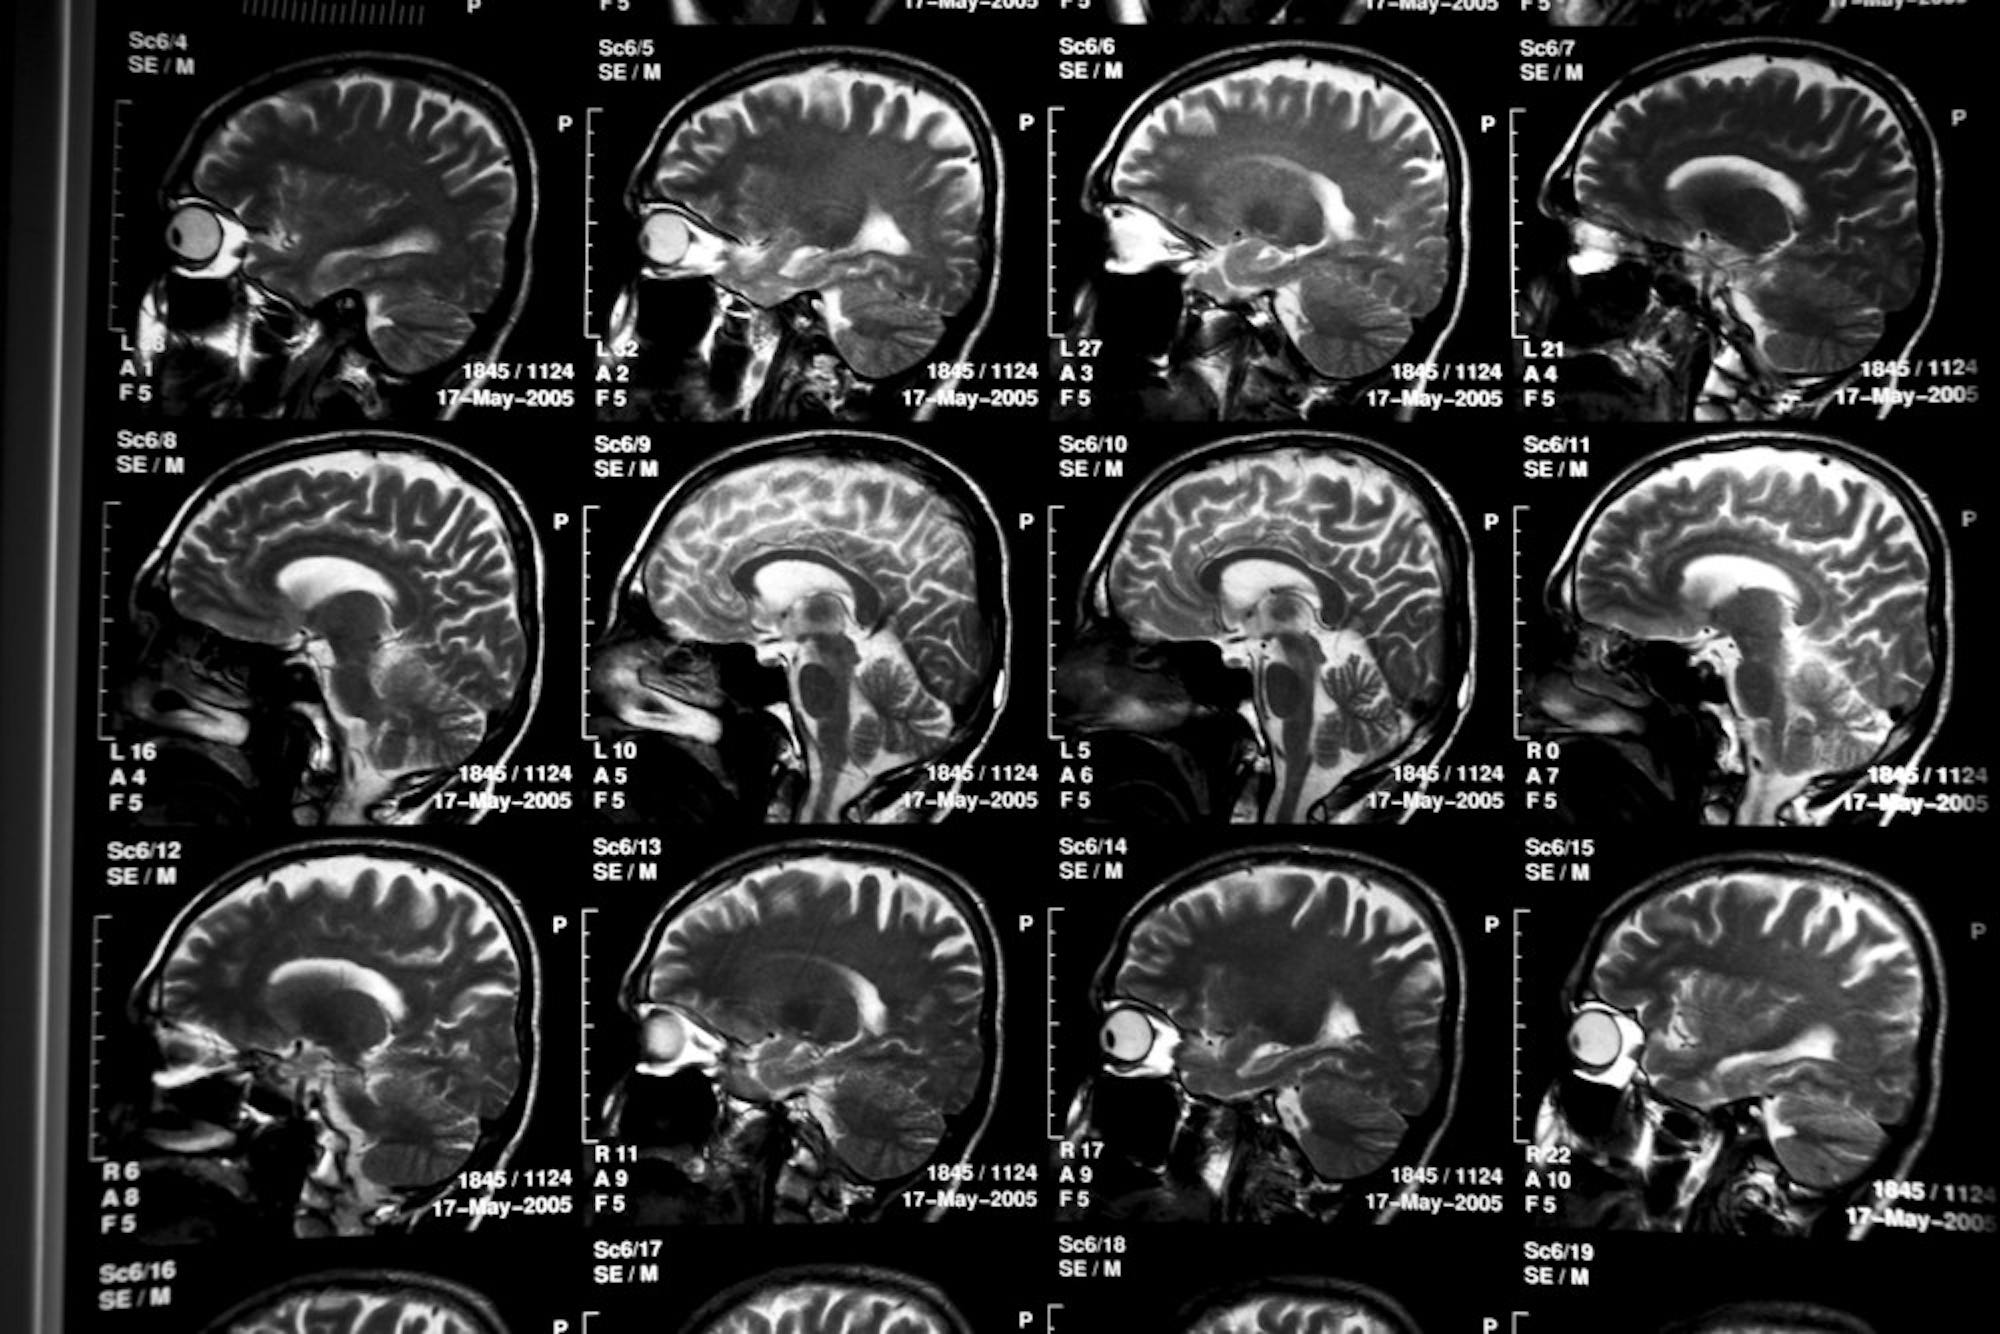

The Tau protein is known to support the internal skeleton of cells. This network transports nutrients to various parts of the neuron and is therefore vital for keeping the cells alive. Mutations in the Tau gene have been previously shown to reduce nutrients and blood flow in the brain which can lead to neurodegenerative diseases, such as frontotemporal dementia — the death of brain neurons controlling behavior and movement.

Mutations have also been linked to Alzheimer’s disease — the death of brain neurons, cells responsible for receiving sensory input which stores or sends motor commands to muscles. This is what eventually leads to memory loss and cognitive decline.